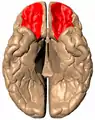

Orbital gyrus shown in red.

Basal surface of cerebrum. Orbital gyrus shown in red.